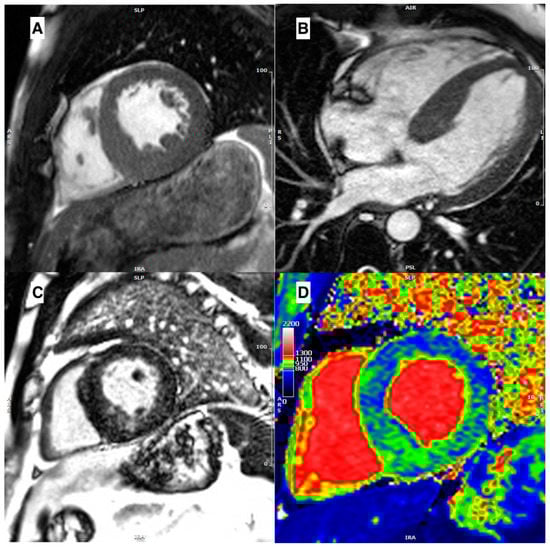

3.3. Role of Late Gadolinium Enhancement

3.4. Role of Parametric Mapping

- Mahrholdt, H.; Wagner, A.; Judd, R.M.; Sechtem, U.; Kim, R.J. Delayed enhancement cardiovascular magnetic resonance assessment of non-ischaemic cardiomyopathies. Eur. Heart J. 2005, 26, 1461–1474. [Google Scholar] [CrossRef]

- Moon, J.C.C.; Reed, E.; Sheppard, M.N.; Elkington, A.G.; Ho, S.Y.; Burke, M.; Petrou, M.; Pennell, D.J. The histologic basis of late gadolinium enhancement cardiovascular magnetic resonance in hypertrophic cardiomyopathy. J. Am. Coll. Cardiol. 2004, 43, 2260–2264. [Google Scholar] [CrossRef]

- Yang, K.; Song, Y.-Y.; Chen, X.-Y.; Wang, J.-X.; Li, L.; Yin, G.; Zheng, Y.-C.; Wei, M.-D.; Lu, M.-J.; Zhao, S.-H. Apical hypertrophic cardiomyopathy with left ventricular apical aneurysm: Prevalence, cardiac magnetic resonance characteristics, and prognosis. Eur. Heart J.—Cardiovasc. Imaging 2020, 21, 1341–1350. [Google Scholar] [CrossRef]

- Habib, M.; Adler, A.; Fardfini, K.; Hoss, S.; Hanneman, K.; Rowin, E.J.; Maron, M.S.; Maron, B.J.; Rakowski, H.; Chan, R.H. Progression of Myocardial Fibrosis in Hypertrophic Cardiomyopathy. JACC Cardiovasc. Imaging 2021, 14, 947–958. [Google Scholar] [CrossRef]

- Maceira, A.M.; Joshi, J.; Prasad, S.K.; Moon, J.C.; Perugini, E.; Harding, I.; Sheppard, M.N.; Poole-Wilson, P.A.; Hawkins, P.N.; Pennell, D.J. Cardiovascular Magnetic Resonance in Cardiac Amyloidosis. Circulation 2005, 111, 186–193. [Google Scholar] [CrossRef]

- Moon, J.C.; Sachdev, B.; Elkington, A.G.; McKenna, W.J.; Mehta, A.; Pennell, D.J.; Leed, P.J.; Elliott, P.M. Gadolinium enhanced cardiovascular magnetic resonance in Anderson-Fabry disease Evidence for a disease specific abnormality of the myocardial interstitium. Eur. Heart J. 2003, 24, 2151–2155. [Google Scholar] [CrossRef] [PubMed]

- Karamitsos, T.D.; Piechnik, S.K.; Banypersad, S.M.; Fontana, M.; Ntusi, N.B.; Ferreira, V.M.; Whelan, C.J.; Myerson, S.G.; Robson, M.D.; Hawkins, P.N.; et al. Noncontrast T1 Mapping for the Diagnosis of Cardiac Amyloidosis. JACC Cardiovasc. Imaging 2013, 6, 488–497. [Google Scholar] [CrossRef] [PubMed]

- Fontana, M.; Banypersad, S.M.; Treibel, T.A.; Maestrini, V.; Sado, D.M.; White, S.K.; Pica, S.; Castelletti, S.; Piechnik, S.K.; Robson, M.D.; et al. Native T1 Mapping in Transthyretin Amyloidosis. JACC Cardiovasc. Imaging 2014, 7, 157–165. [Google Scholar] [CrossRef]

- Baggiano, A.; Boldrini, M.; Martinez-Naharro, A.; Kotecha, T.; Petrie, A.; Rezk, T.; Gritti, M.; Quarta, C.; Knight, D.S.; Wechalekar, A.D.; et al. Noncontrast Magnetic Resonance for the Diagnosis of Cardiac Amyloidosis. JACC Cardiovasc. Imaging 2020, 13, 69–80. [Google Scholar] [CrossRef] [PubMed]

- Maron, M.S.; Appelbaum, E.; Harrigan, C.J.; Buros, J.; Gibson, C.M.; Hanna, C.; Lesser, J.R.; Udelson, J.E.; Manning, W.J.; Maron, B.J. Clinical Profile and Significance of Delayed Enhancement in Hypertrophic Cardiomyopathy. Circ. Heart Fail. 2008, 1, 184–191. [Google Scholar] [CrossRef] [PubMed]

- Bruder, O.; Wagner, A.; Jensen, C.J.; Schneider, S.; Ong, P.; Kispert, E.-M.; Nassenstein, K.; Schlosser, T.; Sabin, G.V.; Sechtem, U.; et al. Myocardial Scar Visualized by Cardiovascular Magnetic Resonance Imaging Predicts Major Adverse Events in Patients With Hypertrophic Cardiomyopathy. J. Am. Coll. Cardiol. 2010, 56, 875–887. [Google Scholar] [CrossRef] [PubMed]

- Chan, R.H.; Maron, B.J.; Olivotto, I.; Pencina, M.J.; Assenza, G.E.; Haas, T.; Lesser, J.R.; Gruner, C.; Crean, A.M.; Rakowski, H.; et al. Prognostic Value of Quantitative Contrast-Enhanced Cardiovascular Magnetic Resonance for the Evaluation of Sudden Death Risk in Patients With Hypertrophic Cardiomyopathy. Circulation 2014, 130, 484–495. [Google Scholar] [CrossRef]

- Todiere, G.; Nugara, C.; Gentile, G.; Negri, F.; Bianco, F.; Falletta, C.; Novo, G.; Di Bella, G.; De Caterina, R.; Zachara, E.; et al. Prognostic Role of Late Gadolinium Enhancement in Patients With Hypertrophic Cardiomyopathy and Low-to-Intermediate Sudden Cardiac Death Risk Score. Am. J. Cardiol. 2019, 124, 1286–1292. [Google Scholar] [CrossRef]

| Disease | Morphological Features | Late Gadolinium Enhancement | Myocardial T1 | ECV |

|---|---|---|---|---|

| Sarcomeric HCM, Pediatric HCM | Several different patterns of hypertrophy Apical aneurysm Crypts Papillary\mitral abnormalities SAM\LVOT obstruction | Mid-wall in hypertrophied segments | Increased only in fibrotic areas | Increased only in fibrotic areas |

| Amyloidosis | Concentrical pseudo-hypertrophy Thickened LA wall Pericardial effusion | Low-difference signal intensity blood-cavity Diffuse subendocardial | Diffusely increased | Diffusely increased |

| Fabry disease | Diffuse hypertrophy (80%), asymmetrical | Inferolateral mid-wall (only in late stage) | Diffusely decreased (increased in LGE areas) | Diffusely decreased (increased in LGE areas) |

| Hypertensive heart disease | Usually, concentric hypertrophy with wall thickness not exceeding 16 mm Rarely, SAM/LVOT obstruction | No LGE | Normal or slightly increased | Normal or slightly increased |

| Mitochondrial cytopathies | Asymmetric (septal) or concentric hypertrophy | Mid-wall LGE in the inferolateral wall or extending in the majority of myocardial segments | Increased, particularly in segments with LGE | Increased, particularly in segments with LGE |

| Glycogen storage disorders | Diffuse or focal myocardial hypertrophy | Patchy mid-wall LGE in septum and insertion point or extending diffusely | Increased | Increased |